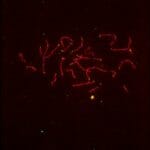

Sperm Chromosome Aneuploidy

Sperm Chromosome Aneuploidy